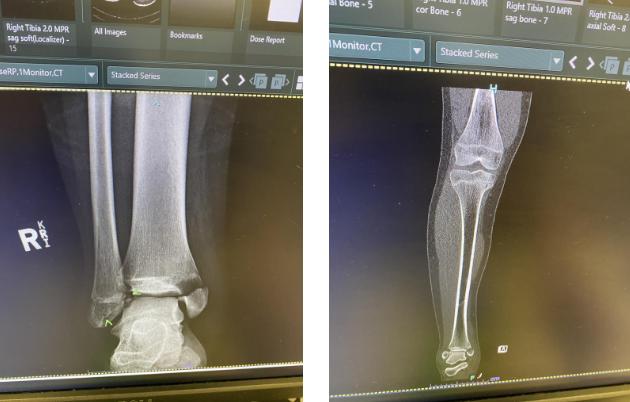

到医院检查后,发现她的腿和脚踝骨折了四块骨头。本周二,她接受了手术,目前精神状态仍然非常好。

他说:“她的胫骨底部折断,一块胫骨脱落,然后用两颗螺丝重新拧紧。”

“她还折断了距骨的两个部分,骨头已经被粘回去了,她的脚踝也有很多损伤。”